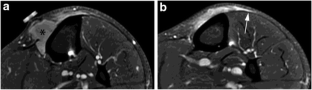

Recurrence of a soft tissue sarcoma typically manifests as a round or oval mass at imaging, and recurrent high-grade soft tissue sarcomas generally enlarge relatively rapidly. We present a case of high-grade undifferentiated pleomorphic sarcoma in the calf of a 48-year-old male that recurred as a thin, curvilinear “tail” of enhancing tissue at magnetic resonance imaging (MRI), with extremely indolent growth over a 7-year period. The unusual imaging finding of a slowly enlarging “tail” should not be dismissed as postoperative changes, even for a high-grade soft tissue sarcoma.

Fig. 2